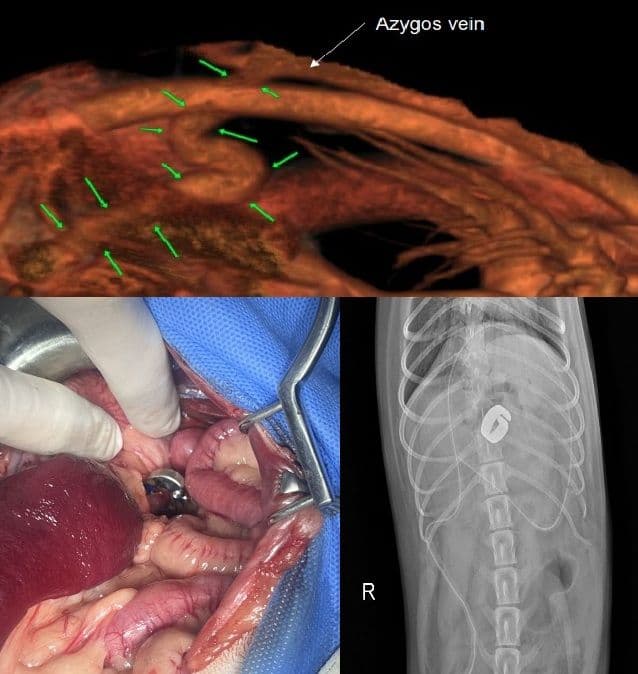

PSS (간문맥 전신 단락)

내외과 협진 고난이도 수술